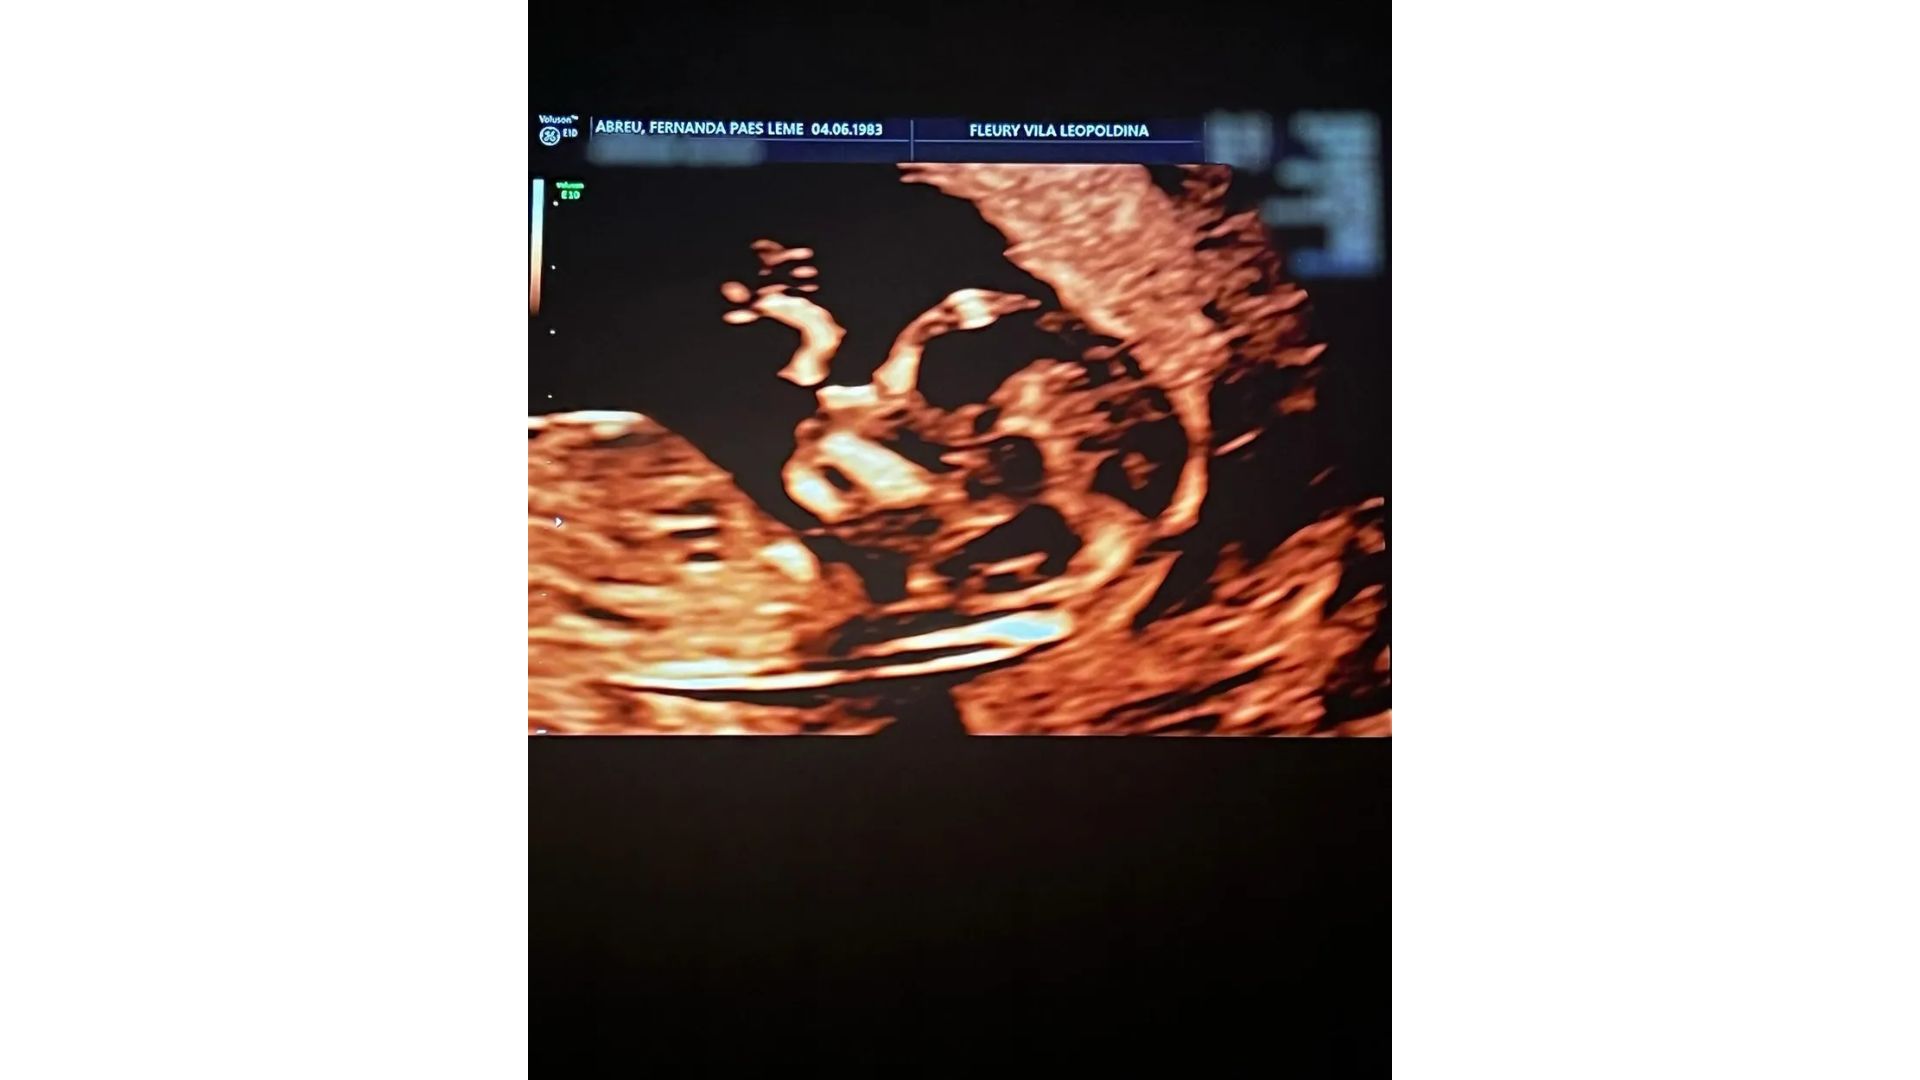

Nesta quinta-feira, 26 de outubro, Fernanda Paes Leme compartilhou o registro de uma ultrassom de sua primeira filha. A mãe já havia feito um exame para confirmar a gravidez, mas agora pôde ver a bebê com detalhes. A menina é fruto do noivado da atriz com Victor Sampaio.

“Primeira selfie da baby mó no ultrassom”, escreveu ela na legenda da publicação feita por meio de seu perfil no Instagram. ‘Mó’ é como o casal se chama entre si, por isso acabaram apelidando a bebê desse jeito.

Nos comentários do post, fãs ficaram encantados com a menina e apontaram uma semelhança entre ela e o pai. “De perfil tá puxando pro pai”, disse um. “A cara do pai, incrível”, comentou outro. “Já sabemos que ela tem os traços do pai“, escreveu um terceiro.